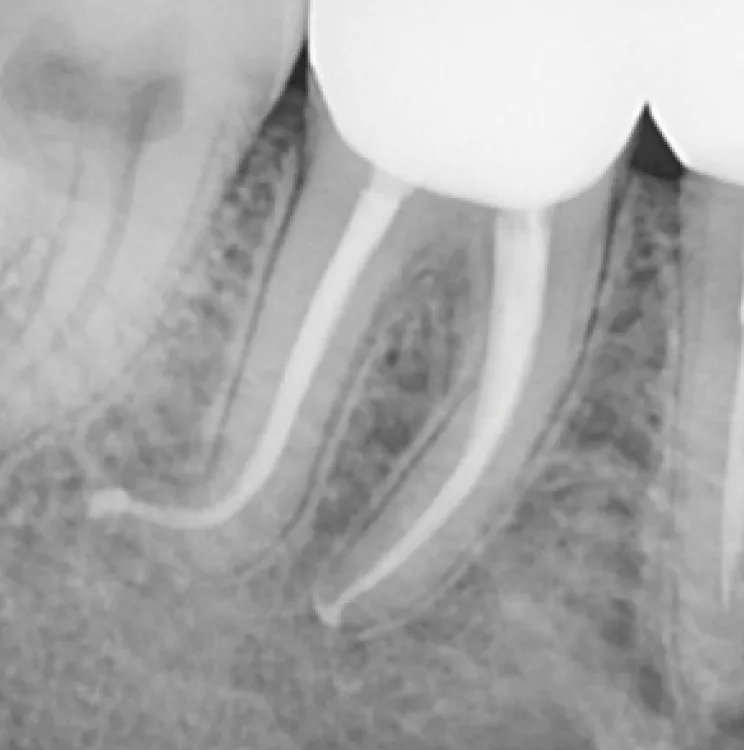

Résultats clinique

1

Avant le traitement

2

Après le traitement